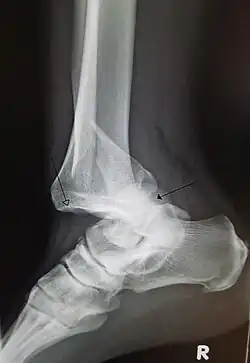

A traumatic dislocation of the tibiotarsal joint of the ankle with distal fibular fracture. Open arrow marks the tibia and the closed arrow marks the talus. | |

A joint dislocation, also called luxation, occurs when there is an abnormal separation in the joint, where two or more bones meet.[1] A partial dislocation is referred to as a subluxation. Dislocations are commonly caused by sudden trauma to the joint like during a car accident or fall. A joint dislocation can damage the surrounding ligaments, tendons, muscles, and nerves.[2] Dislocations can occur in any major joint (shoulder, knees, hips) or minor joint (toes, fingers). The most common joint dislocation is a shoulder dislocation.[1]